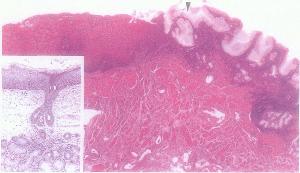

(4)肛管處,有強大的肌環稱為肛直腸環,由肛門內括約肌、肛門外括約肌淺、深部、肛提肌、直腸縱肌組成。此環對肛管起著極其重要的括約作用,損傷將導致大便失禁。肛門內括約肌無括約肌功能,僅有協助排便的作用。肛門外括約肌由橫紋肌構成,受意識支配,排便時鬆弛。